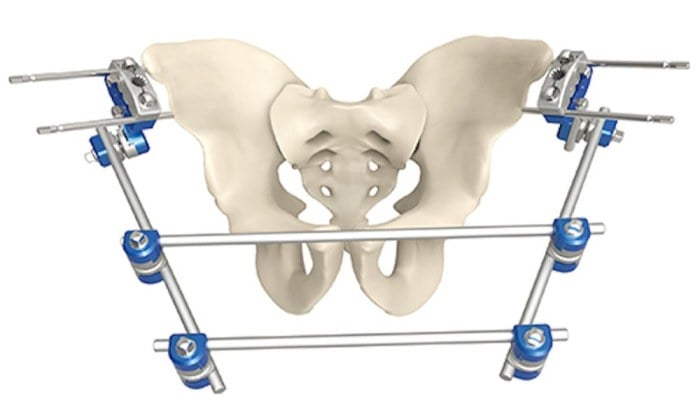

I'm working on a story where a character has a pelvic fracture, and no, it's not one of those weird medical fetish things, I promise! But I need to mention him getting a pelvic binder (which he gets prehospital) and a foley catheter. My research says that combination makes sense? It'll likely be in dialogue of a Dr ordering it and then it's just implied that this works out, or otherwise a short mention- so I don't need to describe the details. I could hand-wave it away entirely, not mention it at all. But now it's like this annoying brain gremlin I can't shake: I've been obsessively looking at pictures of these binder things, scratching my head, thinking "How- physically, logistically, spiritually, how?" Have I lost all understanding of male anatomy? Some of those binder things are wide! It's been driving me nuts for weeks and I can't just ask someone without sounding like a weirdo. 😅 Help!